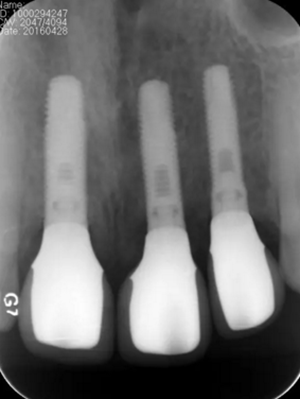

(2)即刻種植、即刻臨時修復(fù)。術(shù)中不翻瓣微創(chuàng)拔除牙根,牙槽 窩骨壁完整。在多級導(dǎo)板輔助下完成種植窩洞制備,植入Bego柱形種植 體,型號分別為:上頜右側(cè)中切牙位點4.1mm×15mm、上頜左側(cè)中切牙 位點?3.75mm×15mm、上頜左側(cè)側(cè)切牙位點3.25mm×15mm,扭矩均為 35N·cm。種植體與唇側(cè)骨壁間隙約2mm,植入Bio-Oss®Collagen骨膠 原。戴入橋用鈦臨時基臺,臨時冠就位順利,自凝樹脂口內(nèi)粘接后適當(dāng)修整 外形,充分磨光,調(diào) 至正中 、前伸 和側(cè)方 與對頜牙均無接觸。術(shù)后 根尖片顯示種植體位置、方向良好。

圖13 術(shù)后即刻根尖片

圖17 術(shù)后6個月根尖片

圖24 最終修復(fù)后即刻根尖片